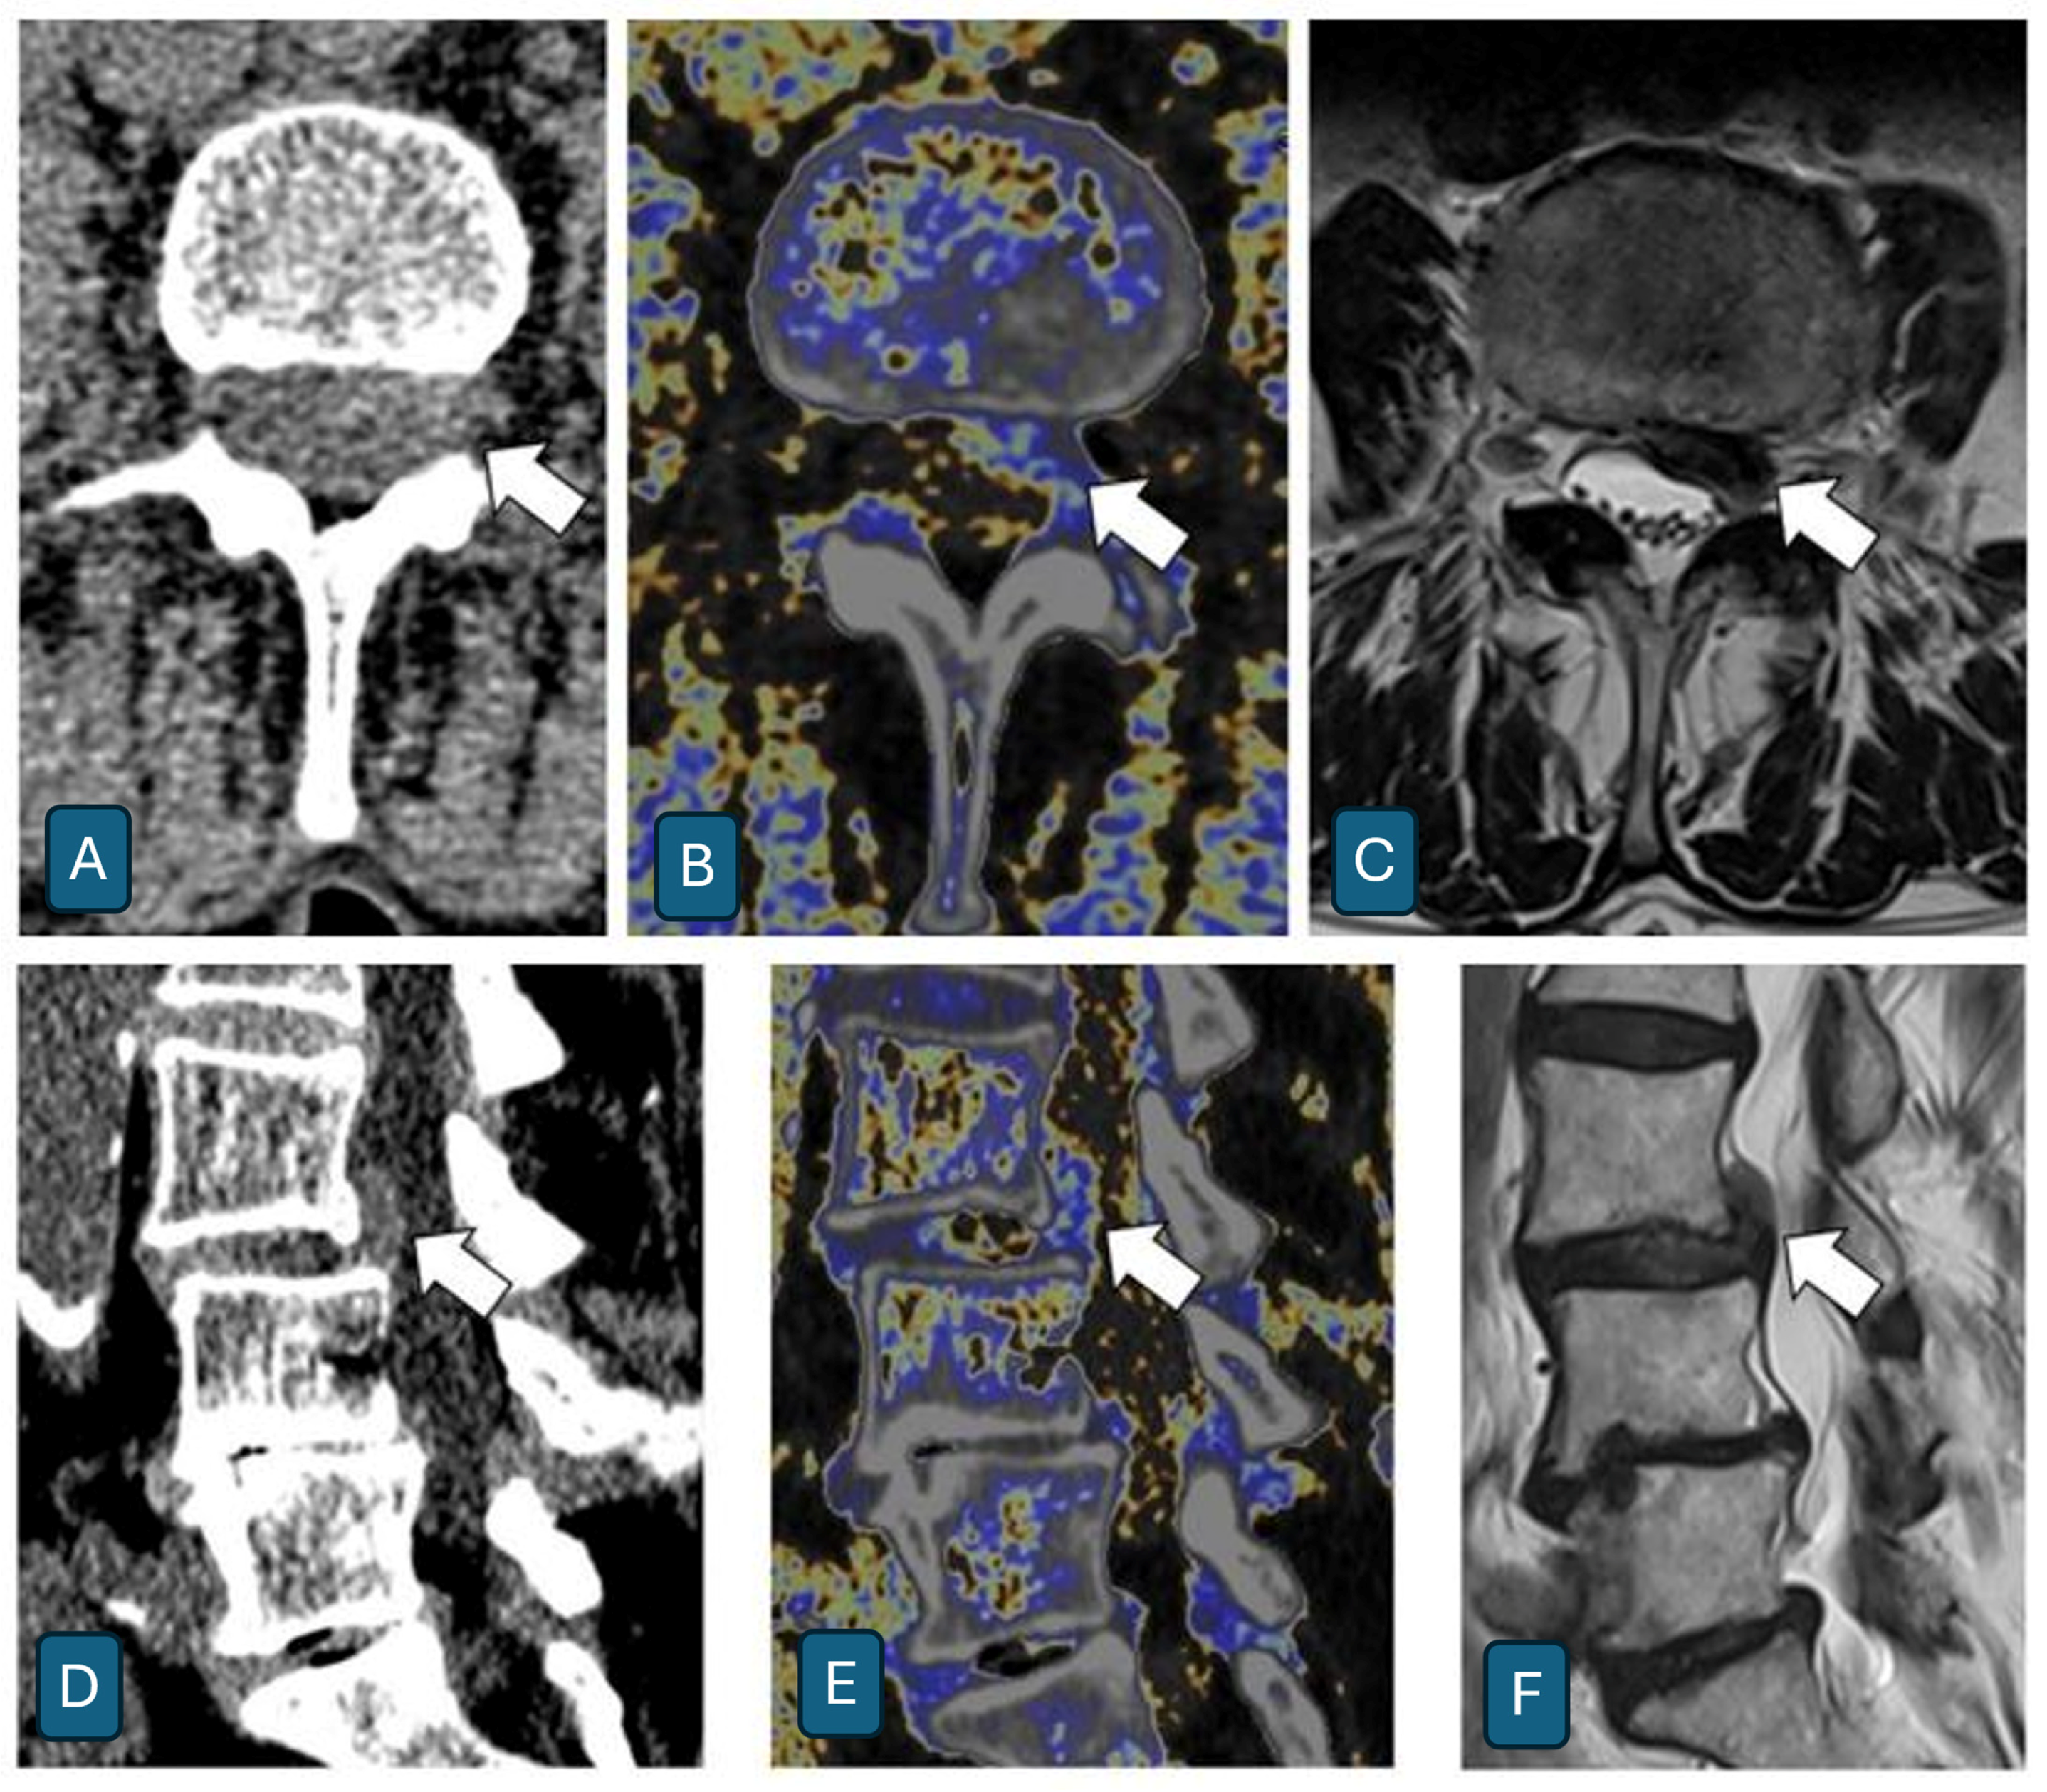

- Shim, E.; Kim, B.H.; Kang, W.Y.; Hong, S.J.; Kang, C.H.; Ahn, K.S.; Lee, H.; Kwack, T.J. Diagnostic performance of electron-density dual-energy CT in detection of cervical disc herniation in comparison with standard gray-scale CT and virtual non-calcium images. Eur. Radiol. 2022, 32, 2209–2220. [Google Scholar] [CrossRef] [PubMed] [PubMed Central]

- Booz, C.; Nöske, J.; Martin, S.S.; Albrecht, M.H.; Yel, I.; Lenga, L.; Gruber-Rouh, T.; Eichler, K.; D’Angelo, T.; Vogl, T.J.; et al. Virtual Noncalcium Dual-Energy CT: Detection of Lumbar Disk Herniation in Comparison with Standard Gray-scale CT. Radiology 2019, 290, 446–455. [Google Scholar] [CrossRef] [PubMed]